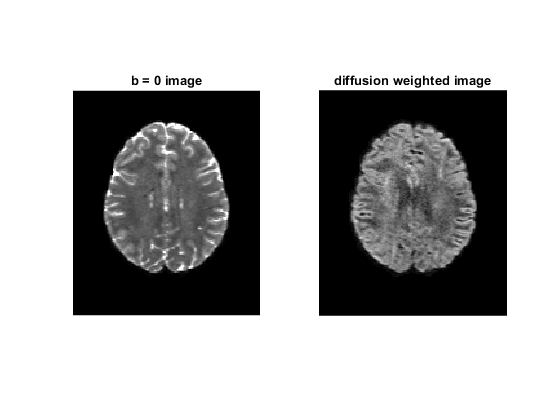

figure;

subplot(1, 2, 1)

imshow(rot90(data(:, :, 35, 1)), [0, 10000])

title('b = 0 image');

subplot(1, 2, 2)

imshow(rot90(data(:, :, 35, 2)), [0, 4000])

title('diffusion weighted image');